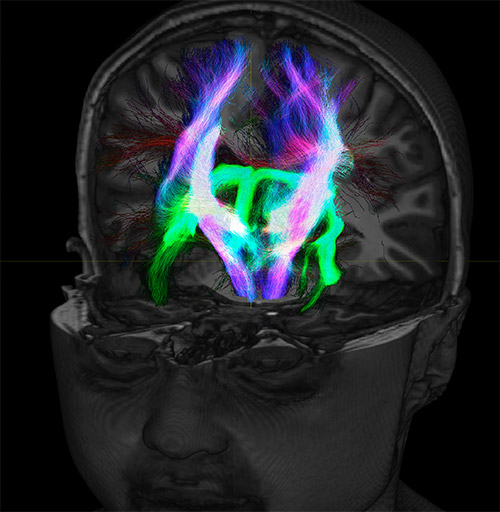

Crossings of the corpus callosum, corticospinal tracts, and the superior longitudinal fasciculus are shown.

Crossing fibers of the corpus callosum bordered by the superior longitudinal fasciculus as well as within in the pons.

Super-resolution directionally encoded color track-density imaging overlaid on T1-weighted structural MRI.